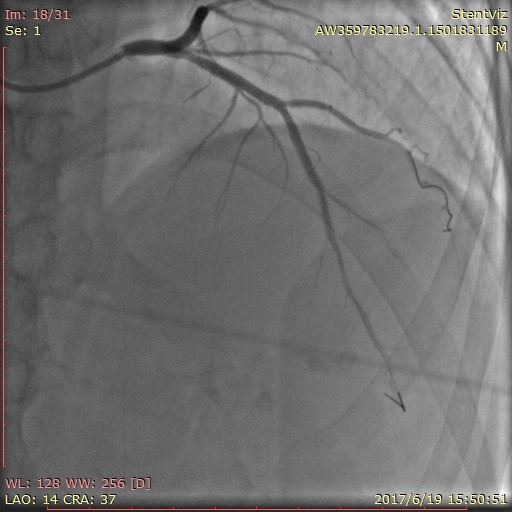

治疗方案及结果: 前降支中远段重度弥漫性狭窄,行支架植入术治疗,术后罪犯血管开通,血流通畅,达TIMI3级。 病例点评及临床价值: 前降支近段支架释放后,发现支架球囊未完全扩张,后扩后情况未明显改善,应用StentViz示:前降支近段支架与远段支架重叠良好,近段支架近端未完全扩张,有“小腰”,呈“狗骨头效应”,同时血管局部钙化斑块明显。明确情况后,继续加压扩张后,支架完全扩张,血流通畅达TIMI3级。 在本病例中,术中StentViz即刻评价了支架释放效果,精准的显示了两支架扩张、重叠和贴壁的情况,把“几乎看不见的支架”精准的呈现了支架的每一个细节,同时也显示了透视和采集不易发现的钙化病变,提高了诊断的精准度,明确了进一步的治疗方案。